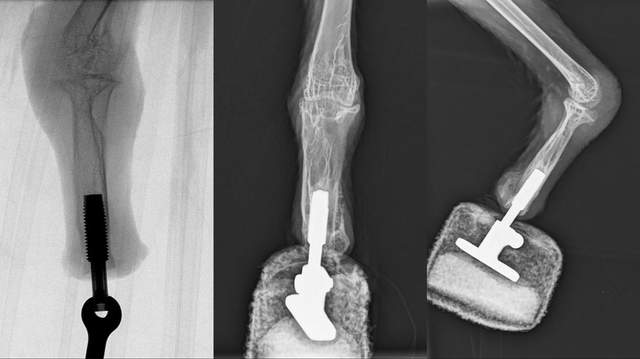

Рентген лапи грифа з інтегрованим у кістку протезом / Фото Medical University of Vienna

У випадку з бородатим грифом команда використовувала метод, відомий як остеоінтеграція. Сутність метода в тому, що основа штучної стопи приєднується безпосередньо до кінця кістки пошкодженої лапи.